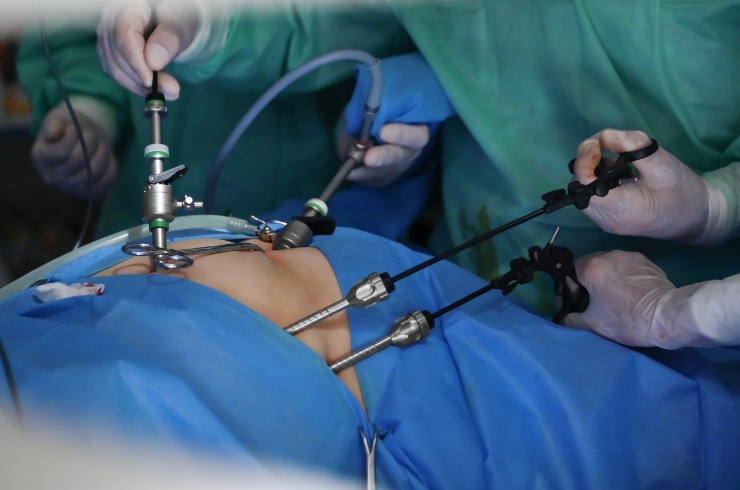

Minimally invasive and open surgical procedures ensuring faster recovery, reduced pain, and improved surgical outcomes.